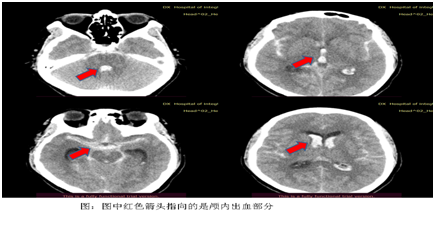

患者女,66岁,工作时突发头痛后,很快进入昏迷状态,由“120”转送至我院急诊。急诊立即开放脑卒中绿色通道,急诊头颅CT提示:弥漫多发蛛网膜下腔出血,双侧脑室、第三脑室、第四脑室内积血。

脑室血肿腔置管成功后,脑血管造影很快显示了导致出血的责任病灶,是右侧椎动脉发出小脑后下动脉段长了一个“跳棋”形态的囊状动脉瘤。(见下图)

手术历时2小时,患者顺利安排进入了重症ICU,因为是微创手术,术后随着患者脑室内的淤血被持续的引流出来,患者在术后七天逐渐苏醒,能够配合。而后复查的头颅CT也显示脑室内出血完全排除。